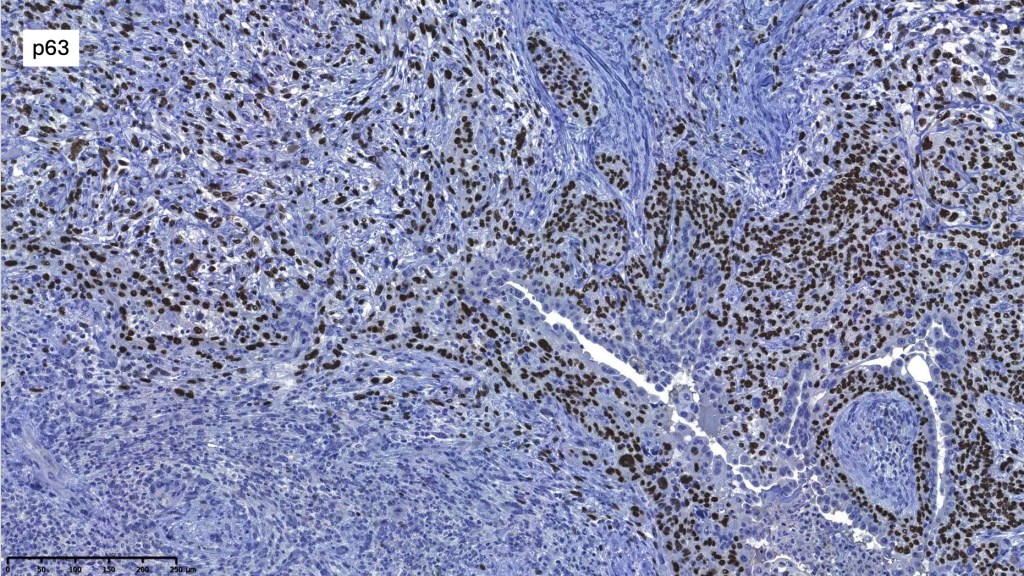

.CK20, p63, TTF-1, PSA, ER, PR -ve